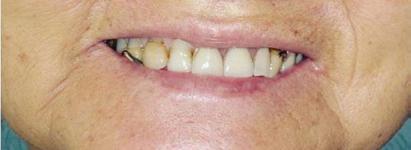

All-On-4 Dental Implants: A Reason To Smile Again

All-on-Four: One Full Arch Of Teeth, Four Dental Implants

To fully understand this remarkable technique for replacing teeth, you should first understand what a dental implant is. An implant is a small titanium screw that fits inside your jawbone and replaces the root-part of a missing tooth. Minor surgery is required to insert the implants. Once the implant is in place, a crown is attached to give you a highly realistic-looking and functional prosthetic tooth.

Here’s where it gets really interesting: You do not need a dental implant for each and every one of your missing teeth. All you need is four precisely placed implants on the top of your mouth, and four on the bottom, to restore your full smile. That’s the beauty of the all-on-four. And because the implant is made of titanium, it has the unique ability to fuse to living bone and function as part of it. So eventually, the dental implant becomes part of the jawbone and serves as a strong, long-lasting foundation for your new teeth.

Besides ensuring that your implants are permanently fixed in place, this bone fusion has another important benefit: it prevents future bone loss in the jaw. This helps to maintain a more youthful facial structure – and better oral health. But perhaps the biggest surprise about the all-on-four is how quickly it can transform your life.